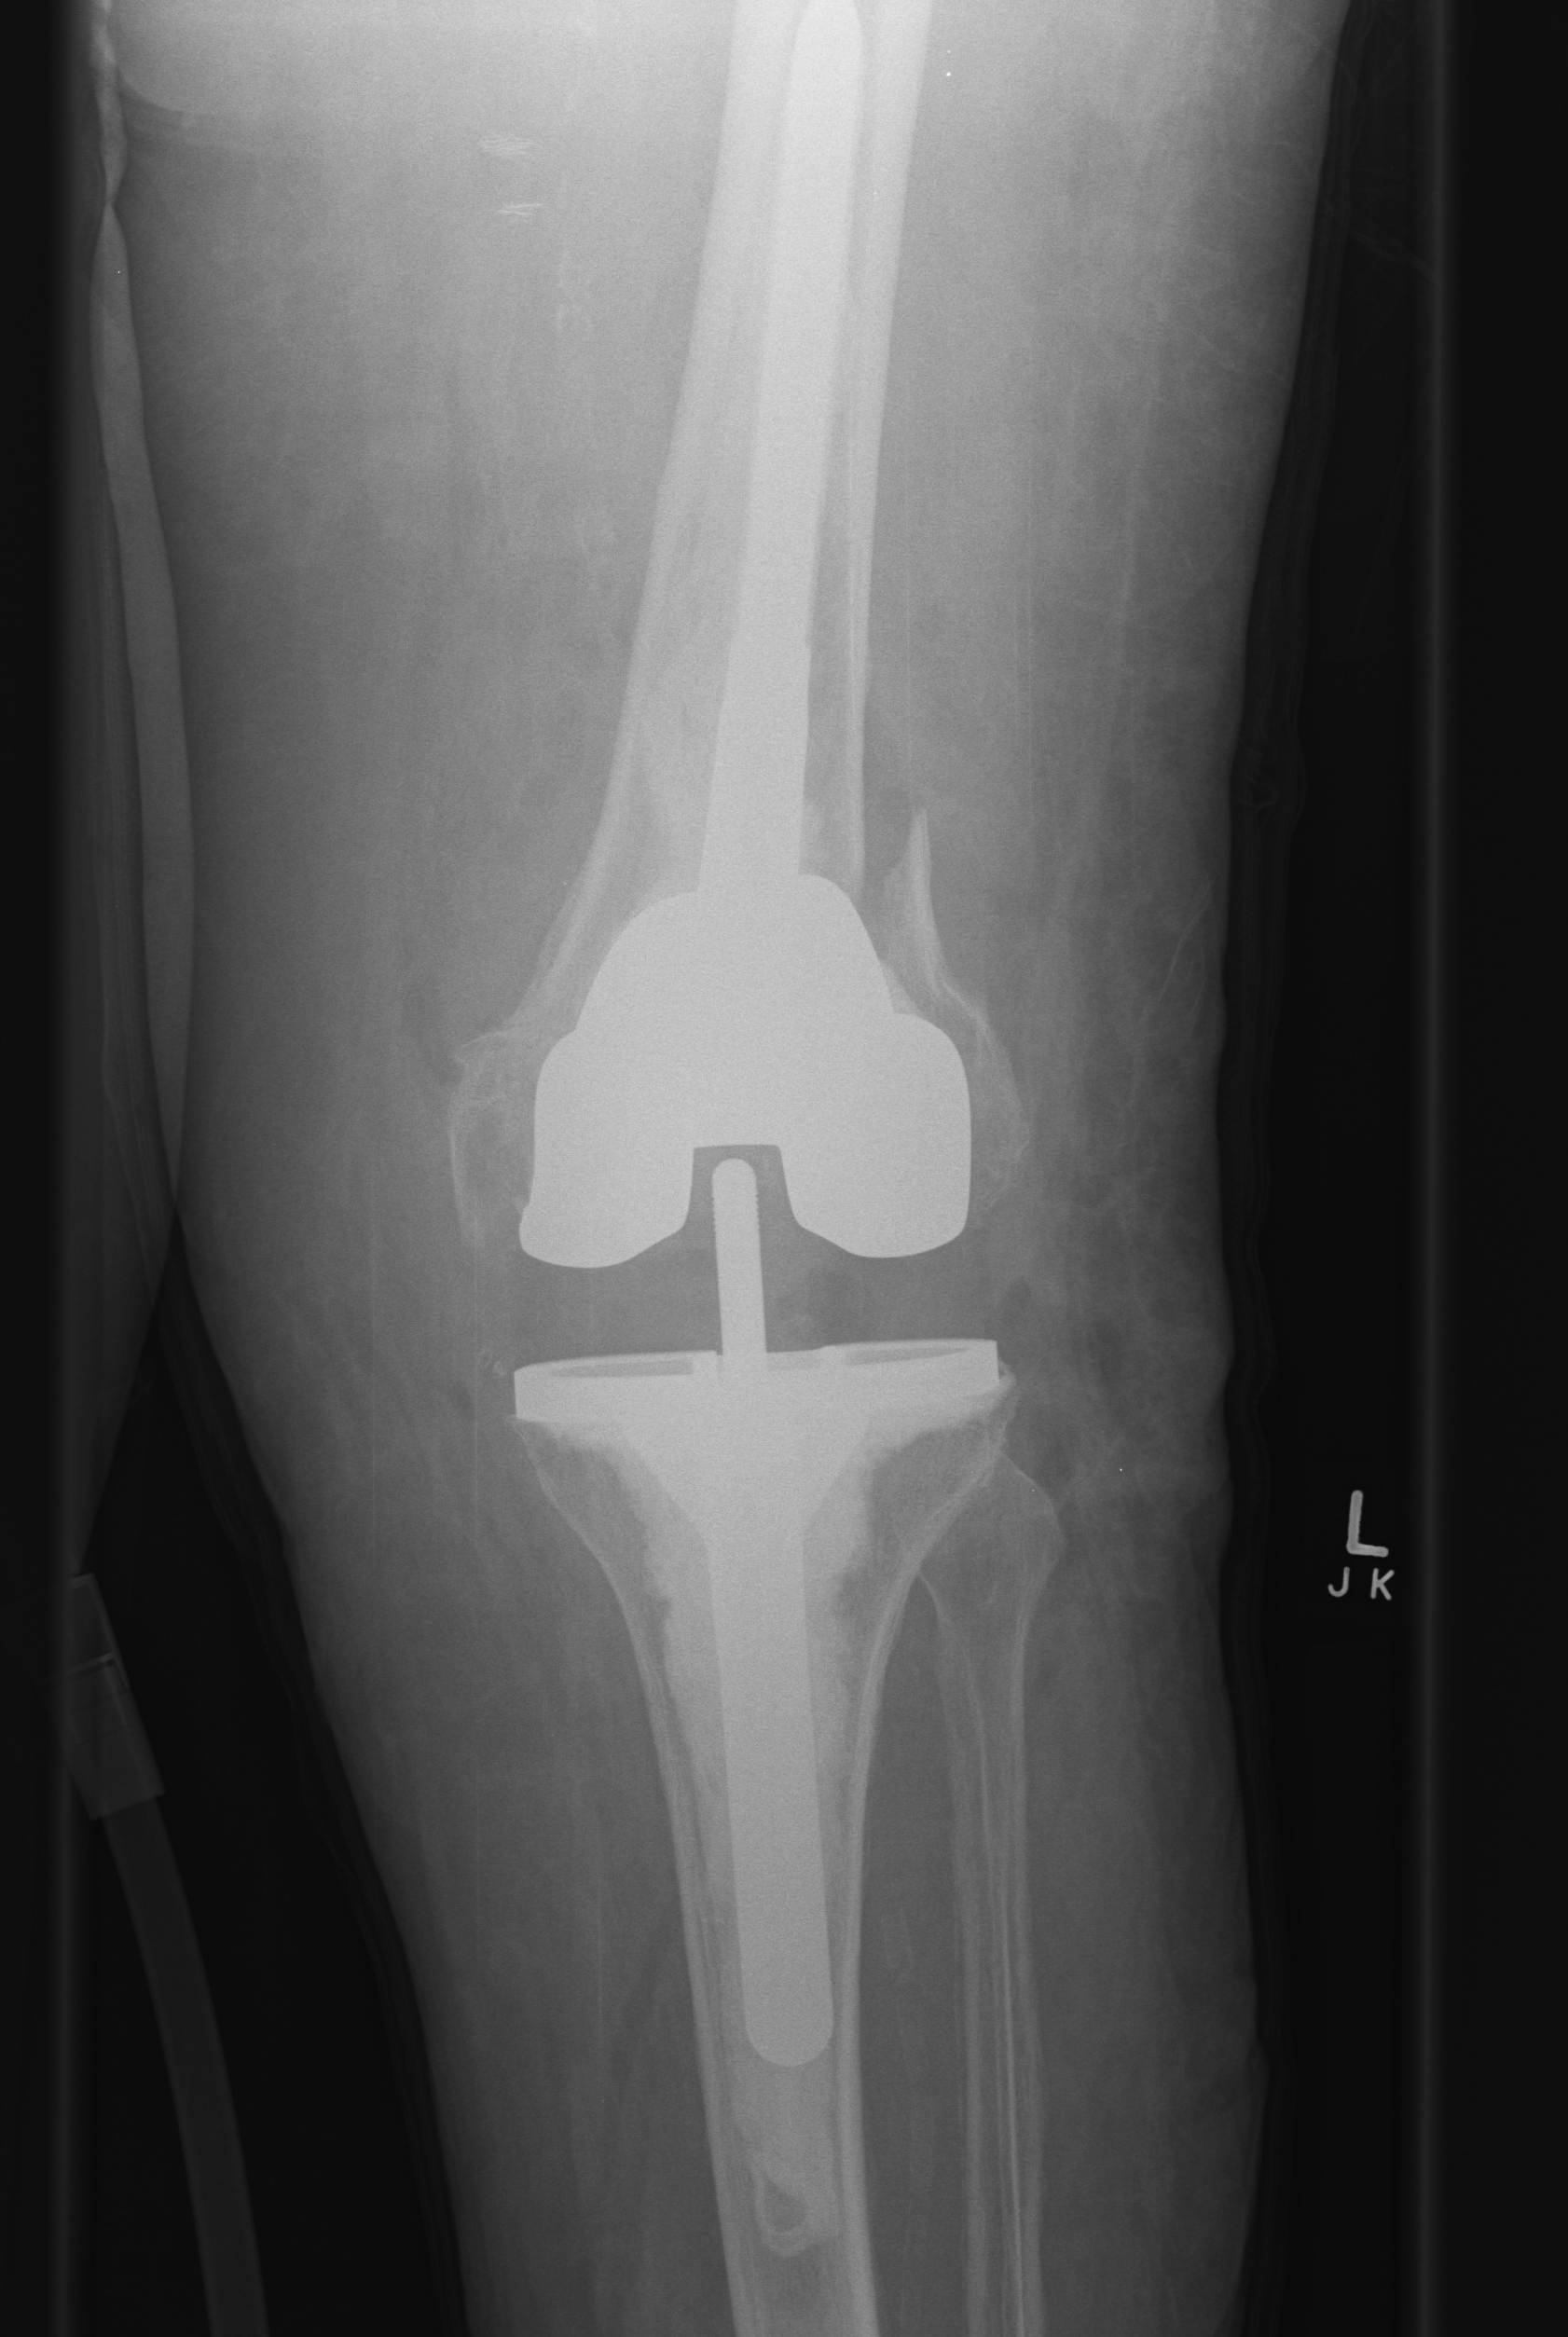

1. Reduce implant loosening

- offset load sharing to diaphysis

- 30% if > 70 mm

Indications

1. Using augments or bone grafting

2. Increased constraint

- VVS / hinge